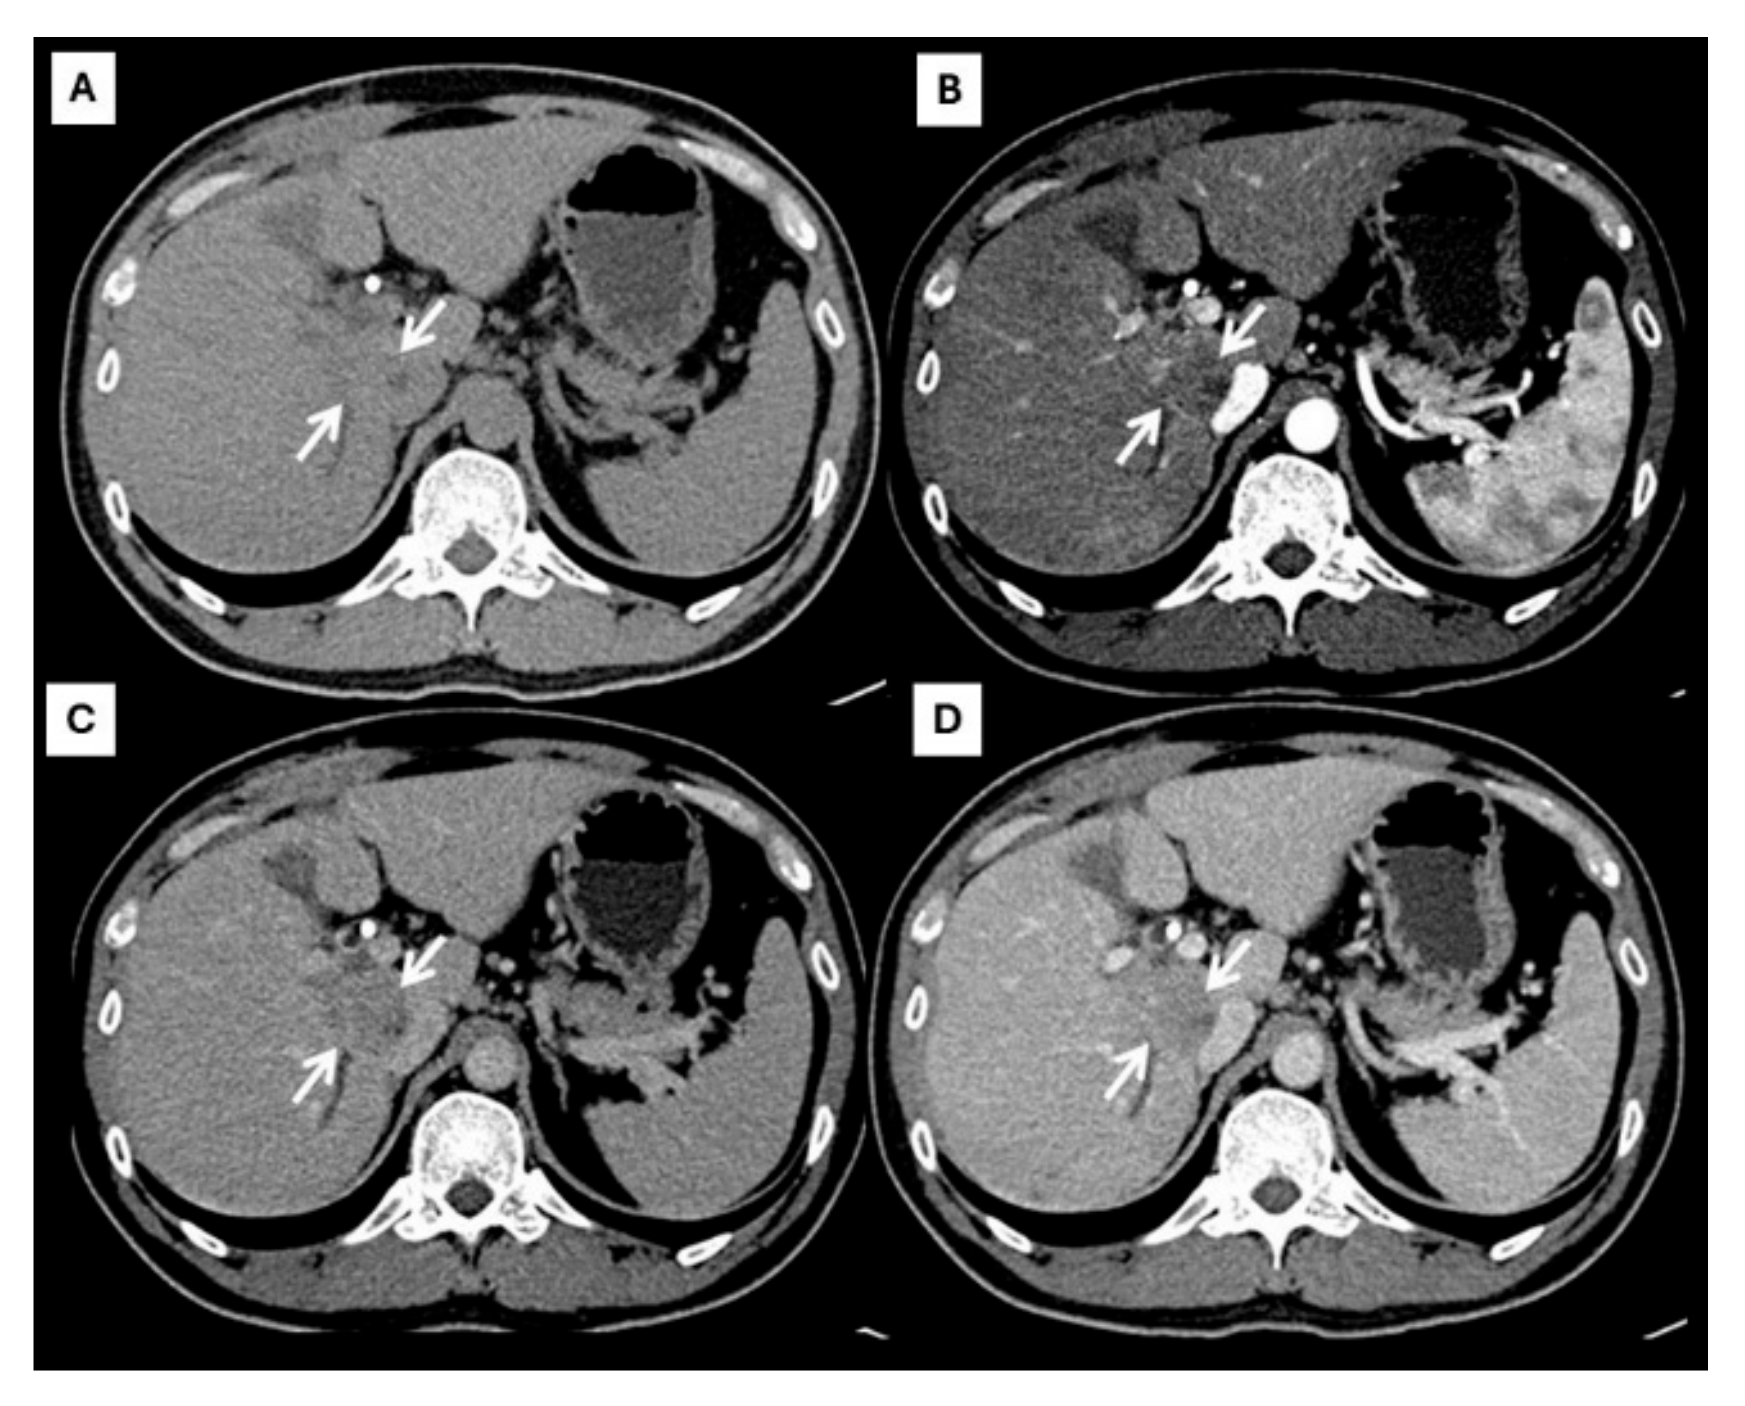

Figure 1.

CT findings of typical HCC. Pre-contrast (A), arterial (B), portal venous (C), and delayed (D) post-contrast sequences demonstrate a mass with non-rim arterial hyperenhancement ((B), arrow), washout appearance in later phase ((C), arrow), and the presence of an enhancing capsule ((D), arrow).